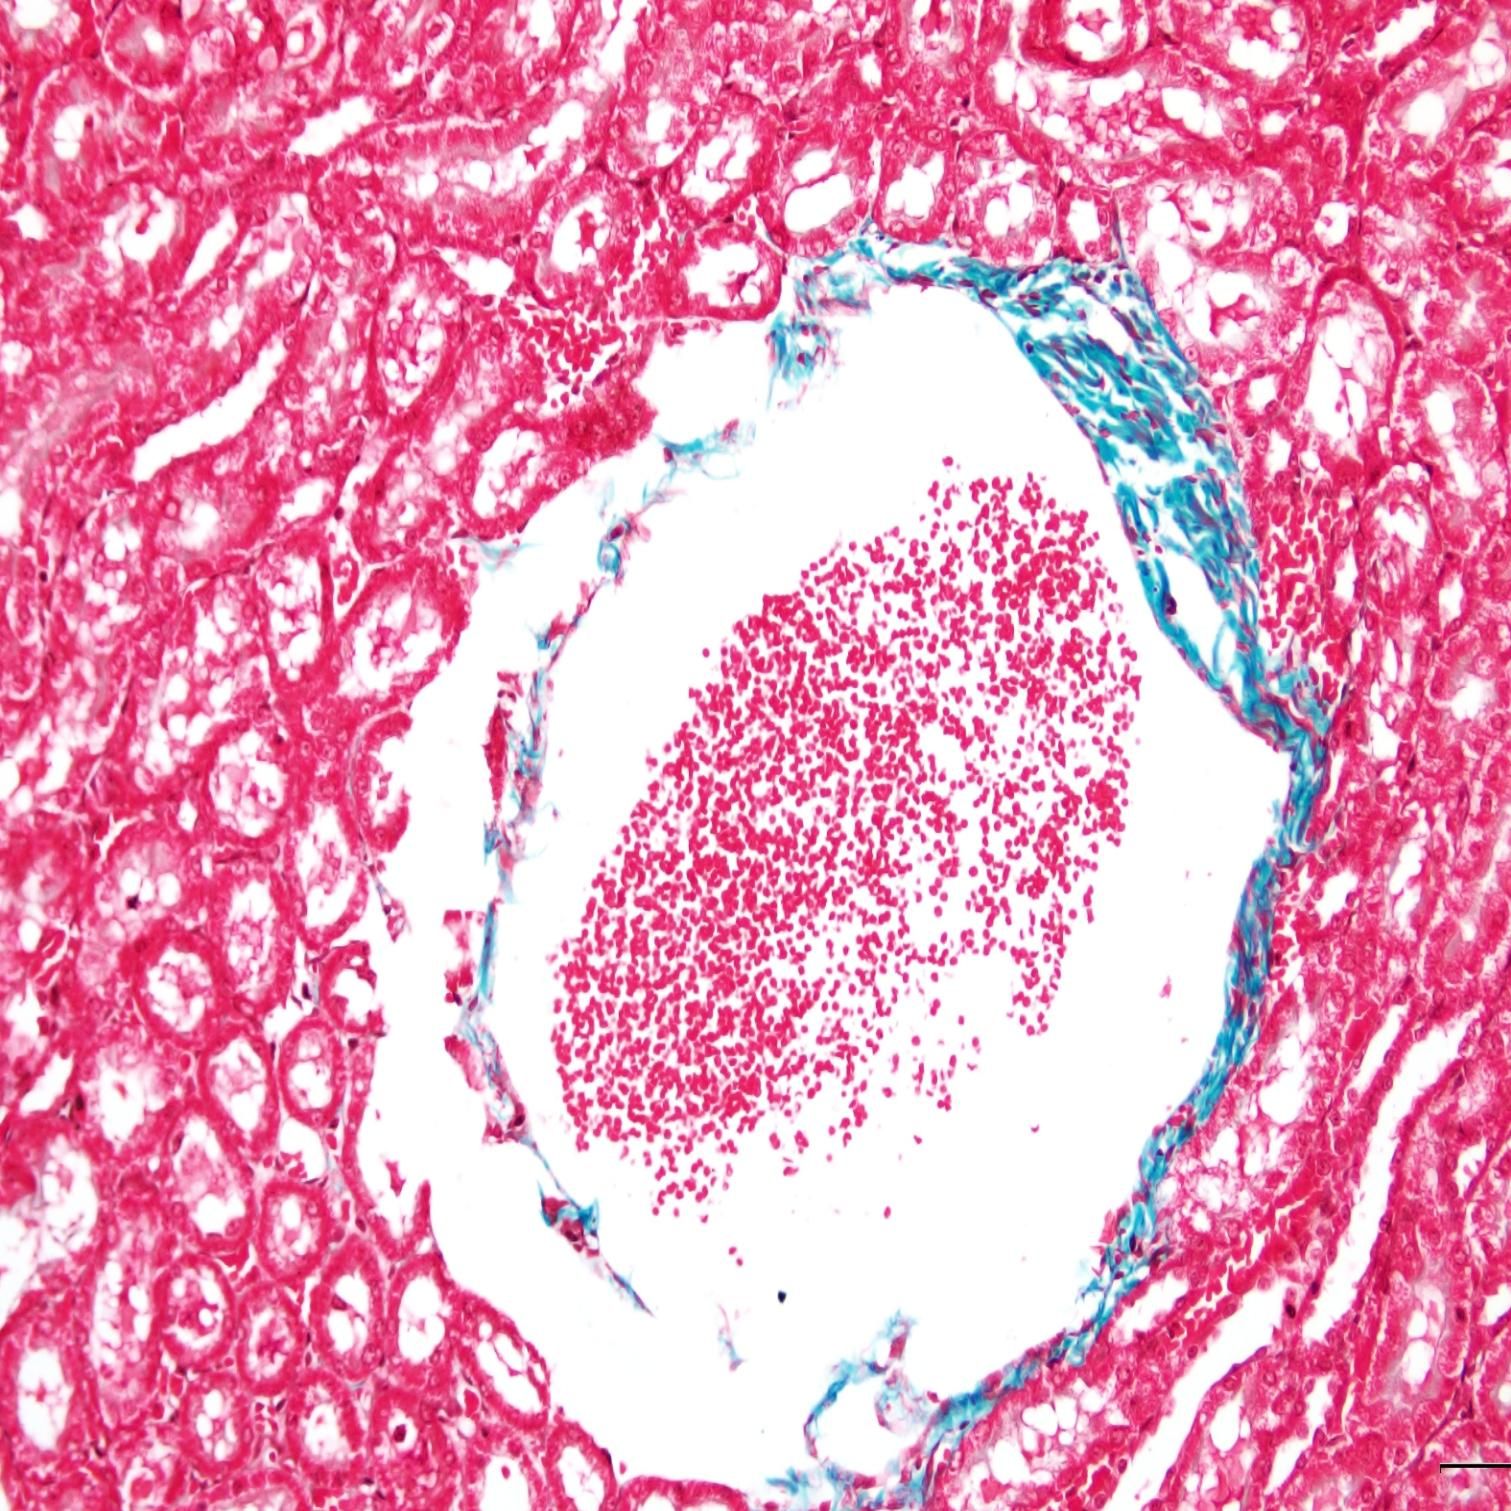

MASSON染色

●觀察與分析:通過顯微鏡觀察染色后的組織切片,分析膠原纖維、肌纖維等組織結(jié)構(gòu)的分布、形態(tài)和排列情況。

小鼠纖維化